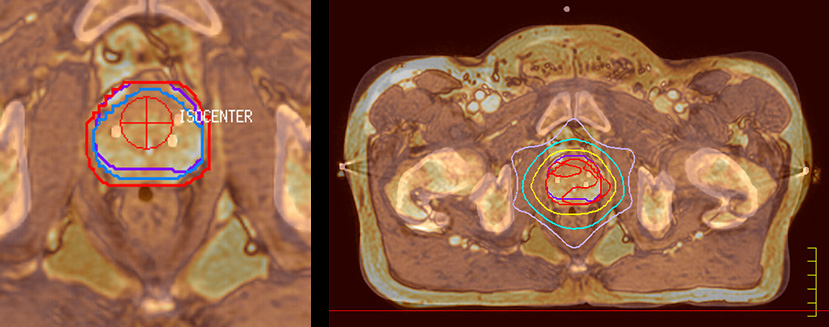

“The biggest problem for CT-based planning, especially in prostate, is you can’t see the cancer very well,” says Dr. Stevens. “On CT it can be quite challenging to see the edge of the prostate especially at the apex. When the edge of the prostate can’t be delineated well on CT, radiation oncologists will increase their margins a little bit so they don’t miss it, but that can also increase toxicity.” “Using MR, the prostate is well delineated. We quickly see the edges of cancerous tumors like in prostate cancer, and as normal structures can be defined, we can optimize the treatment plan to protect these organs and their normal function. This can potentially improve the outcome. And it improves workflow as well. We can contour more quickly, confident that the tumor is going to be in the field.” “The Ingenia 3.0T MR scanner provides high resolution allowing us to make scans fast for the patients. It also gives the potential to include methods like MR spectroscopy and diffusion weighted Imaging, which we’re in the process of doing right now,” Dr. Stevens adds.

“When a patient registers, first CT simulation and MR simulation are done, followed by CT-MR registration on Pinnacle3. Then the target and normal organ delineation is performed on MR images. Meanwhile we create a reference CT image for online treatment and localization correction. During the treatment phase we can perform additional MRI scans to visualize the anatomy changes and create an adaptive plan. This plan basically adapts the treatment plan to the changes.” “Along with its great benefits, MR has introduced some new challenges,” Dr. Stevens says. “Radiation therapy teams generally have no experience with MR. The Philips training helped us to implement fully the things we can do with the Ingenia MR-RT system. So the training, as well as having a good MR physicist, is critical.”

“There are some general challenges in RT imaging – even with CT – such as imaging geometry and positioning accuracy. Positioning is extremely important in RT, because we need reproducibility between imaging and treatment position. We also need accurate geometry so we can be sure our treatment plan is properly delivered during the treatment,” says Dr Yan. “The Ingenia MR-RT configuration includes an external laser positioning system for patient alignment and a flat tabletop for imaging the patient in treatment position. Ingenia MR-RT also came with a special QA package for regular monitoring of precision. Our Ingenia 3.0T scanner achieves good geometric accuracy – within a millimeter for most patients – and the phantom measurement is even better,” he adds. “Ingenia’s wide 70 cm bore is valuable to easily accommodate immobilization devices needed in RT,” says Dr. Stevens. “With a small bore MR scanner you can’t get the RT immobilization devices into the scanner properly; the large bore makes it easy to image patients in their immobilization device.”